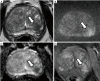

In recent years, active surveillance has been increasingly adopted as a conservative management approach to low and sometimes intermediate risk prostate cancer, to avoid or delay treatment until there is evidence of higher risk disease. A number of studies have investigated the role of multiparametric magnetic resonance imaging (mpMRI) in this setting. MpMRI refers to the use of multiple MRI sequences (T2-weighted anatomical and functional imaging which can include diffusion-weighted imaging, dynamic contrast enhanced imaging, spectroscopy). Each of the parameters investigates different aspects of the prostate gland (anatomy, cellularity, vascularity, etc.). In addition to a qualitative assessment, the radiologist can also extrapolate quantitative imaging biomarkers from these sequences, for example the apparent diffusion coefficient from diffusion-weighted imaging. There are many different types of articles (e.g., reviews, commentaries, consensus meetings, etc.) that address the use of mpMRI in men on active surveillance for prostate cancer. In this paper, we compare original articles that investigate the role of the different mpMRI sequences in men on active surveillance for prostate cancer, in order to discuss the relative utility of the different sequences, and combinations of sequences. We searched MEDLINE/PubMed for manuscripts published from inception to 1st December 2017. The search terms used were (prostate cancer or prostate adenocarcinoma or prostatic carcinoma or prostate carcinoma or prostatic adenocarcinoma) and (MRI or NMR or magnetic resonance imaging or mpMRI or multiparametric MRI) and active surveillance. Overall, 425 publications were found. All abstracts were reviewed to identify papers with original data. Twenty-five papers were analysed and summarised. Some papers based their analysis only on one mpMRI sequence, while others assessed two or more. The evidence from this review suggests that qualitative assessments and quantitative data from different mpMRI sequences hold promise in the management of men on active surveillance for prostate cancer. Both qualitative and quantitative approaches should be considered when assessing mpMRI of the prostate. There is a need for robust studies assessing the relative utility of different combinations of sequences in a systematic manner to determine the most efficient use of mpMRI in men on active surveillance.